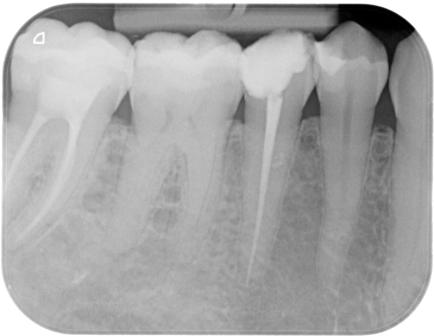

Nel nostro Studio impieghiamo un sistema radiografico computerizzato, il Vista Scan Plus della Dürr che consente di ottenere immagini di alta qualità (vedi confronto analogico/digitale) con dosi radiogene sensibilmente più basse per il paziente.

Con Vistascan Plus siamo in grado di ottenere, nel giro di pochi minuti, tutte le immagini che ci servono per un corretto ausilio diagnostico: bitewing, endorali, ortopantomografie, teleradiografie.